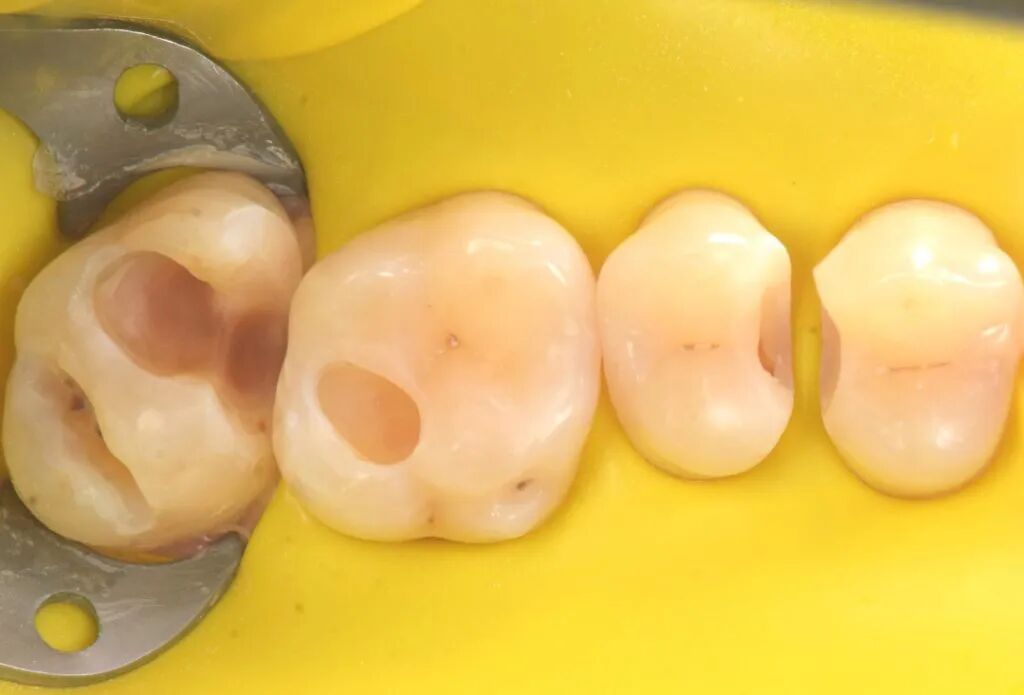

图1. 一位患者主诉左上后牙食物嵌塞咬合不适。左上象限(从第一前磨牙至第二磨牙)龋病情况如图。